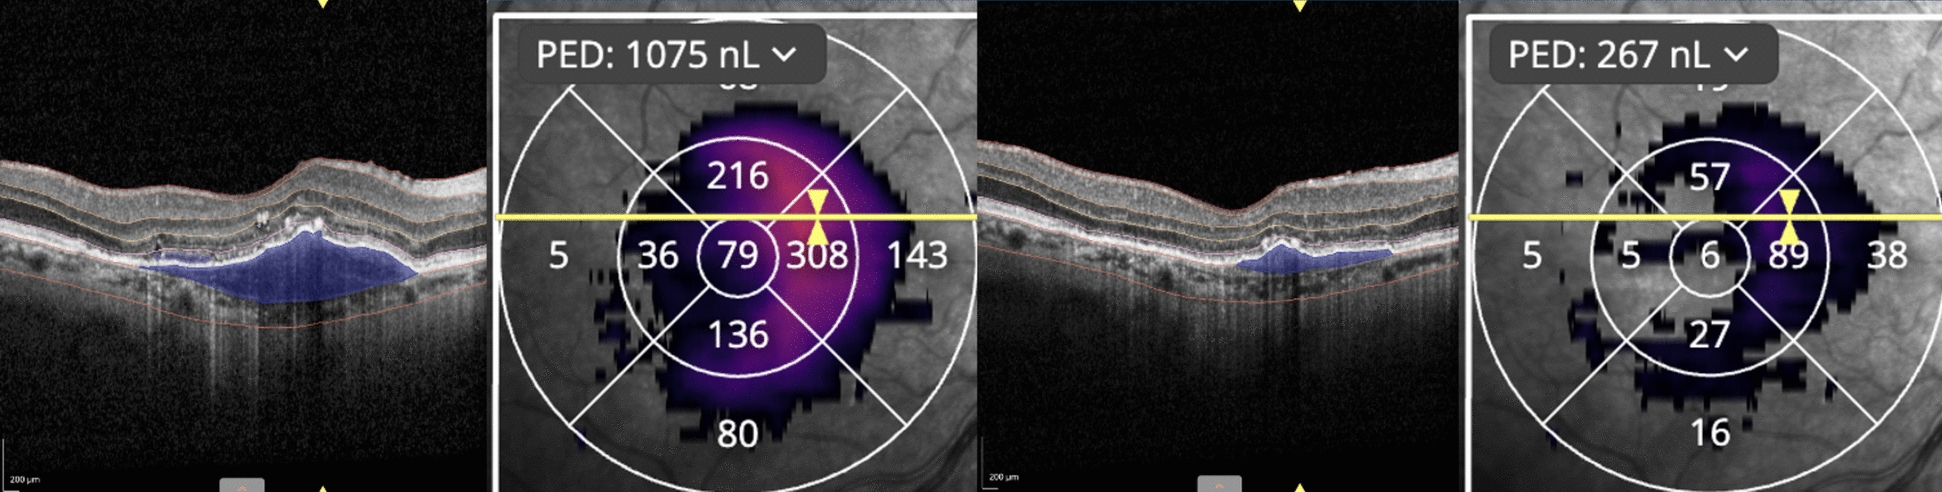

Methods: A retrospective case series study of 22 eyes with unresponsive CNV, despite monthly intravitreal treatment (mean number of pre-faricimab injections: 35.52 ± 17.12). We evaluated therapeutic response in eyes with persistent intra/subretinal fluid (IRF/SRF) unresponsive to anti-VEGF double-dose (DD) monotherapy (4-mg aflibercept) and/or simultaneous DD anti-VEGF (4-mg aflibercept) with steroids (triamcinolone). Best-corrected visual acuity (BCVA), intraocular pressure (IOP), and optical coherence tomography (OCT) measurements of central retinal thickness (CRT) were recorded for 7 follow-ups. Baseline and follow-up OCTs were examined by an AI-developed platform (Discovery OCT Fluid and Biomarker Detector, RetinAI AG, Switzerland) to measure the volume of IRF, SRF, and pigment epithelium detachment (PED) in nanoliters (nL) and CRT in micrometers (μm). Paired t-test compared these parameters at baseline and after treatment. OCTA analysis of CNV before and after treatment with faricimab was conducted using Angio-Tool software.

Results: Anatomic outcomes included mean CRT reduction of -25.3 μm (p = 0.0118) at month-1, -16.15 μm (p = 0.0414) at month-4, and -26.36 μm (p = 0.0129) after the 7th follow-up. AI-assisted software analysis showed a significant reduction of IRF, SRF, and PED volume at multiple time points after initiating faricimab. There was a non-significant improvement in BCVA.